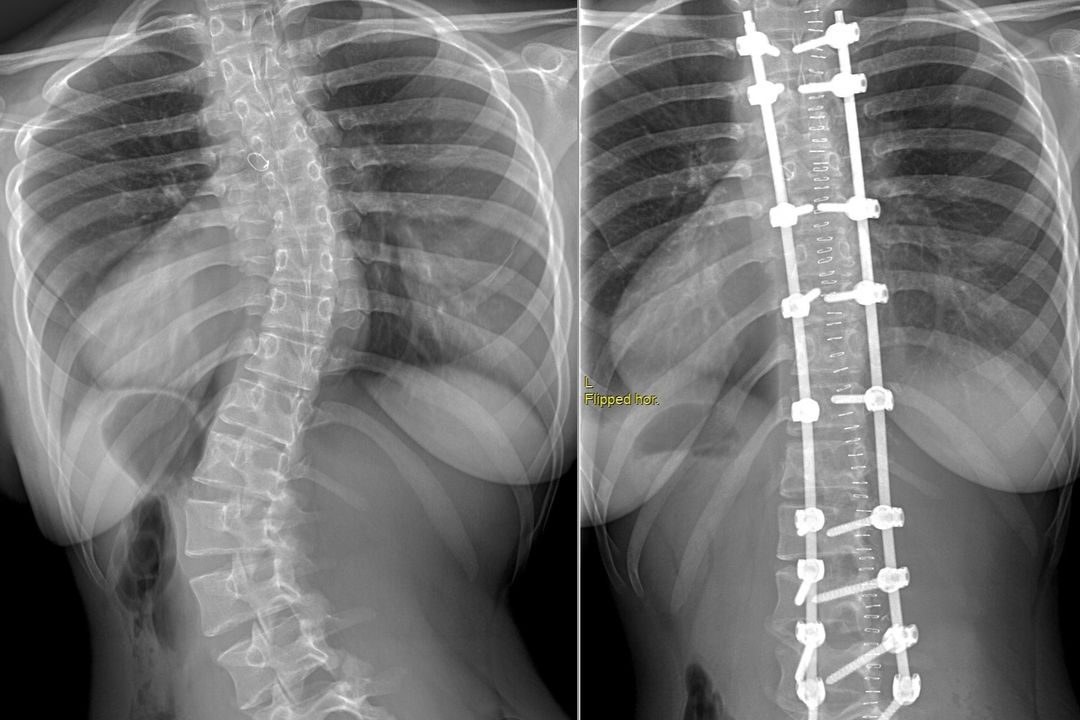

В 2020 году семья Колупановых переехала в Новосибирск. Полина с мамой обратились в НИИТО к хирургу-вертебрологу Михаилу Михайловскому. Школьнице диагностировали идиопатический прогрессирующий декомпенсированный левосторонний поясничный сколиоз IV степени с грудным противоискривлением.

Операция длилась почти 4 часа. Хирурги скорректировали деформацию и зафиксировали позвоночник в правильном положении с помощью специальной металлической конструкции.